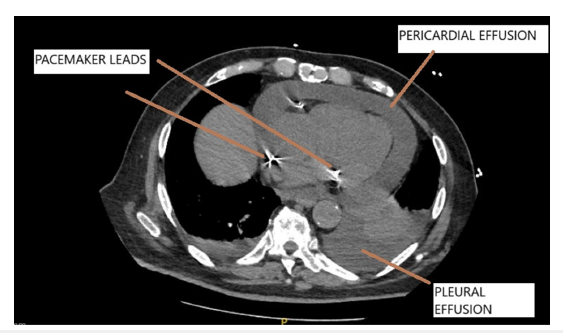

The right ventricular lead had a screw in tip (active fixation) while the lead in right atrial appendage was tined (passive fixation). Post procedure chest X ray was satisfactory and patient was uneventfully discharged on 3rd post op day. Stitch removal was done on 10th post op day and patient had no complaints then. 3 weeks later the patient presented with breathlessness which had rapidly progressed over the last 3-4 days. At presentation he was orthopneic. There was low grade fever, no cough or expectoration and chest x ray revealed blunting of the costophrenic angles. Physical examination revealed a temperature of 100.4-degree Fahrenheit, pulse rate of 130/minute, blood pressure of 110/70mmHg, respiratory rate of 33/minute, and raised JVP with no evidence of pedal edema. Chest auscultation revealed decreased breath sounds at bilateral lung bases and normal heart sounds with evidence hypoxemia (SPO2 of 82% on room air). An echocardiogram revealed moderate circumferential pericardial effusion with maximum localization posterolateral to the left ventricle. Effusion along the right ventricle was mild and pacing leads were seen in the right atrium and right ventricle with mild lead induced tricuspid regurgitation. There was no evidence of cardiac tamponade. On pacemaker interrogation all parameters were found to be satisfactory (lead impedance and threshold were within normal limits). A high-resolution CT scan of the thorax revealed evidence of moderate pericardial effusion, small to moderate pleural effusion and no evidence of extracardiac migration of the pacemaker leads (Figure 1). The fluid in the pericardial cavity had an attenuation value of 40 Hounsfield units suggestive of an exudative nature of the pericardial collection. His complete blood counts, KFT, procalcitonin were normal however ESR was 68mm at the end of 1st hour and CRP was 122.48mg/L. A pleural tap was done under Ultrasound guidance and biochemical examination of the aspirate was suggestive of an exudative etiology using Light’s criteria. The total cells count was 500cu/ mm(P-78.0%) with pleural fluid/serum protein of 0.8 and pleural fluid LDH/serum LDH of 1.1. Pleural fluid ADA level was normal (4IU/L) and TB PCR was negative. Microbiological examination of the Pleural fluid was negative for bacteria, fungus, and tuberculosis and there was no evidence of malignant cells on cytological examination. In view of the above findings the possibility of PCIS though rare was strongly considered. The patient was started on tab Colchicine 0.5mg twice a day. However, by day 10 no significant improvement was noted. In view of the same oral prednisolone 60mg once a day was added following which he showed marked clinical improvement within a week. Prednisolone was tapered over the next 2 weeks and colchicine was discontinued at 2 weeks. All inflammatory parameters normalized and echocardiogram showed complete resolution of pericardial effusion. Patient is doing well at 3 months follow up and review echocardiogram showed no pericardial effusion.

Figure 1:CT chest shows pericardial and bilateral pleural effusion. Pacemaker leads are also seen.